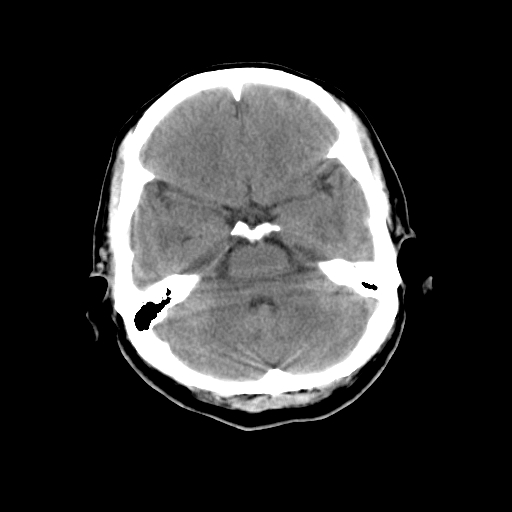

左枕骨松质骨不均匀低密度灶,边缘清楚,考虑良性松质骨性骨瘤可能性大。

以下是引用sunbin在2010-1-6 14:39:00的发言:[br]左枕骨松质骨不均匀低密度灶,边缘清楚,考虑良性松质骨性骨瘤可能性大。

不排除左枕骨嗜酸性肉芽肿可能。